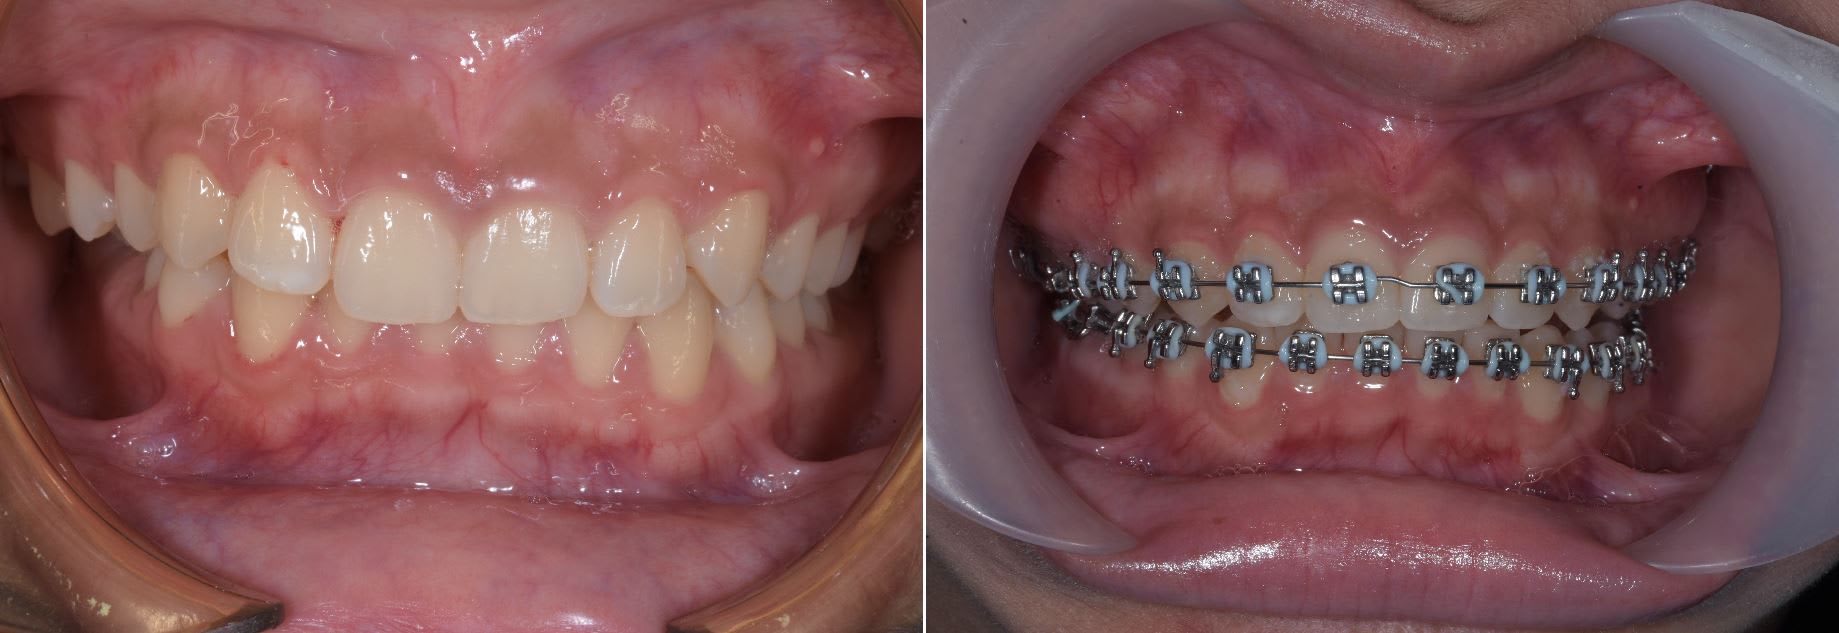

Deux patients vue Samedi dernier , deux cas un peut compliquer et un des deux ou je n'avais jamais vue de cas équivalent. Les deux sont en vois de finalisation pour la partie " hard "

Un cas de cross bite ( déjà montré ) postérieur pas le pire que j'ai eux mais ça reste quand même assez costaux.

Occlusion rétablie du coté cross bite et présque rétablie du coté " normal "

Un cas plus inhabituel Patient class III avec cross bite antérieur. Ici gros espaces en antérieur à la mandible. Vue le coté inhabituel j'ai fait un set up qui m'a indiqué qu'il fallait à la fois mésialer les secteurs postérieur supérieur et inférieure. Traduction pas de mécanique class III classique.

Pour la distalisation j'ai utilisé deux minivisse en palatin avec un fil de 0.8 mm en boucle. Le design est simple , économique , ne necessite pas de matos particulier ( important au Cambodge ) et est très efficace.

Quelque photo avant après. Les pano sont intéressante car elles montre bien que l'on à mesialé l'ensemble des secteurs post, que sa soit à la mandibule ou au maxillaire.